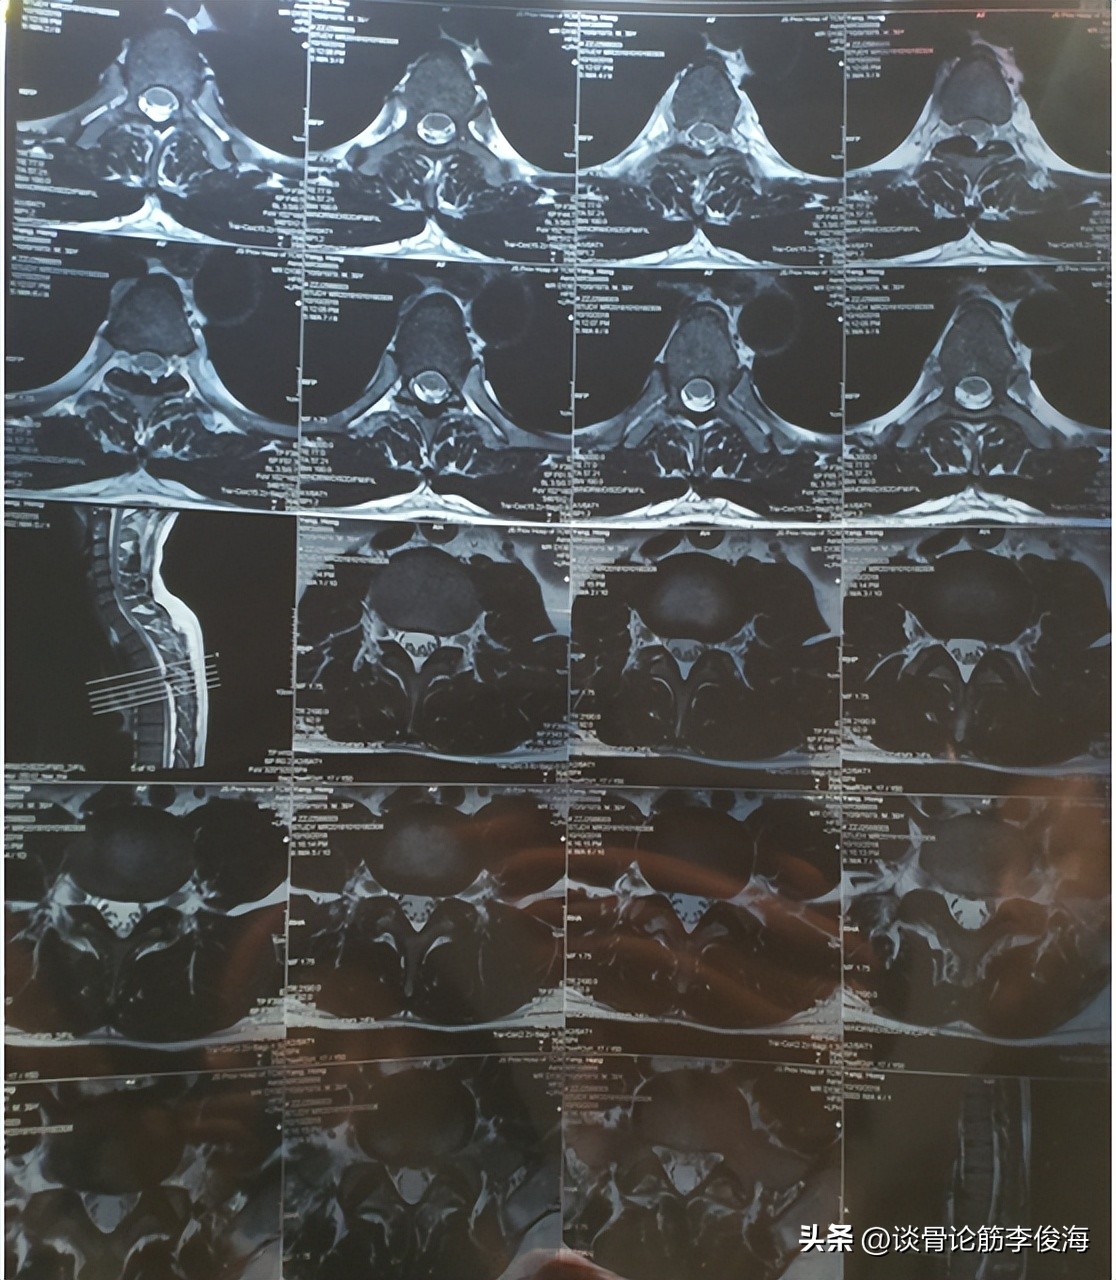

该患者是一名41岁男性,患有颈椎、腰椎间盘突出。他的情况比较复杂,因为一般病人的颈椎、腰椎有问题。他却波及到了胸椎,出现了椎间盘突出,基本上脊椎的各个部位都有,不过经过治疗后恢复得很顺利。